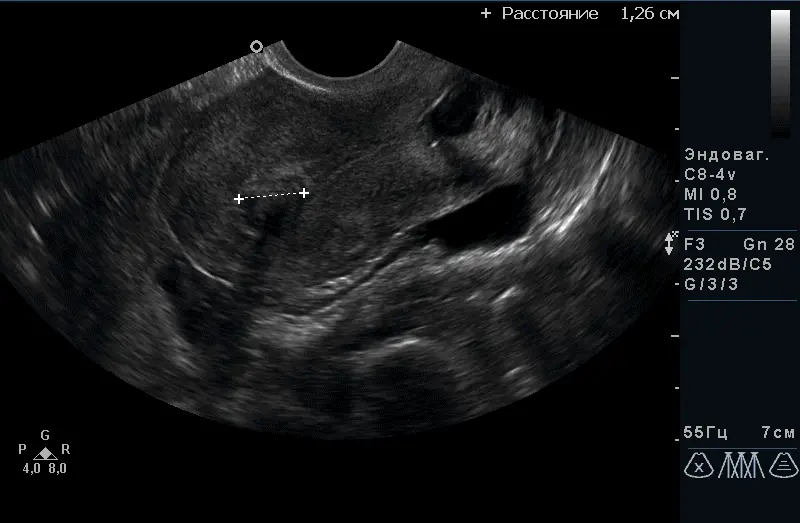

Трансвагінальний доступ є “золотим стандартом” в дослідженні органів малого таза на увазі найкращою візуалізації з найтоншої оцінкою структури, оптимальний метод в діагностиці вагітності на ранніх термінах, оцінці будови плода до 14 тижнів. Датчик розташовується в піхві.

За допомогою УЗД можна побачити і оцінити стан тіла матки, шийки матки, яєчників, маткових труб (при їх патології) і оточуючих їх органів. Є пріоритетним методом дослідження стану судин малого таза. Під час дослідження вимірюються розміри всіх доступних для дослідження органів, оцінюється їх структура і відповідність фазі менструального циклу, оцінка кровопостачання органів і судин.